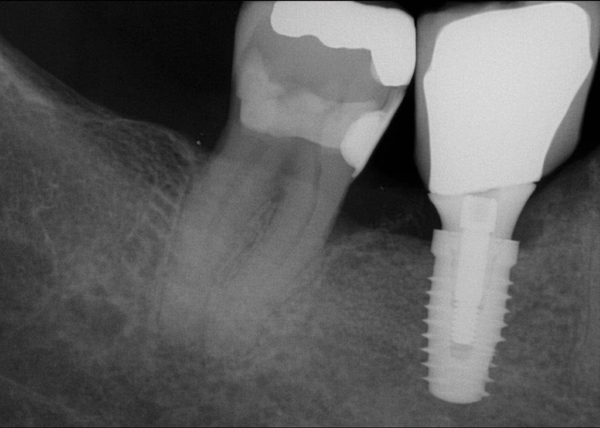

Fig 20. (Case 4) Radiograph of tooth No. 30, which had a hopeless prognosis.

Figure 20